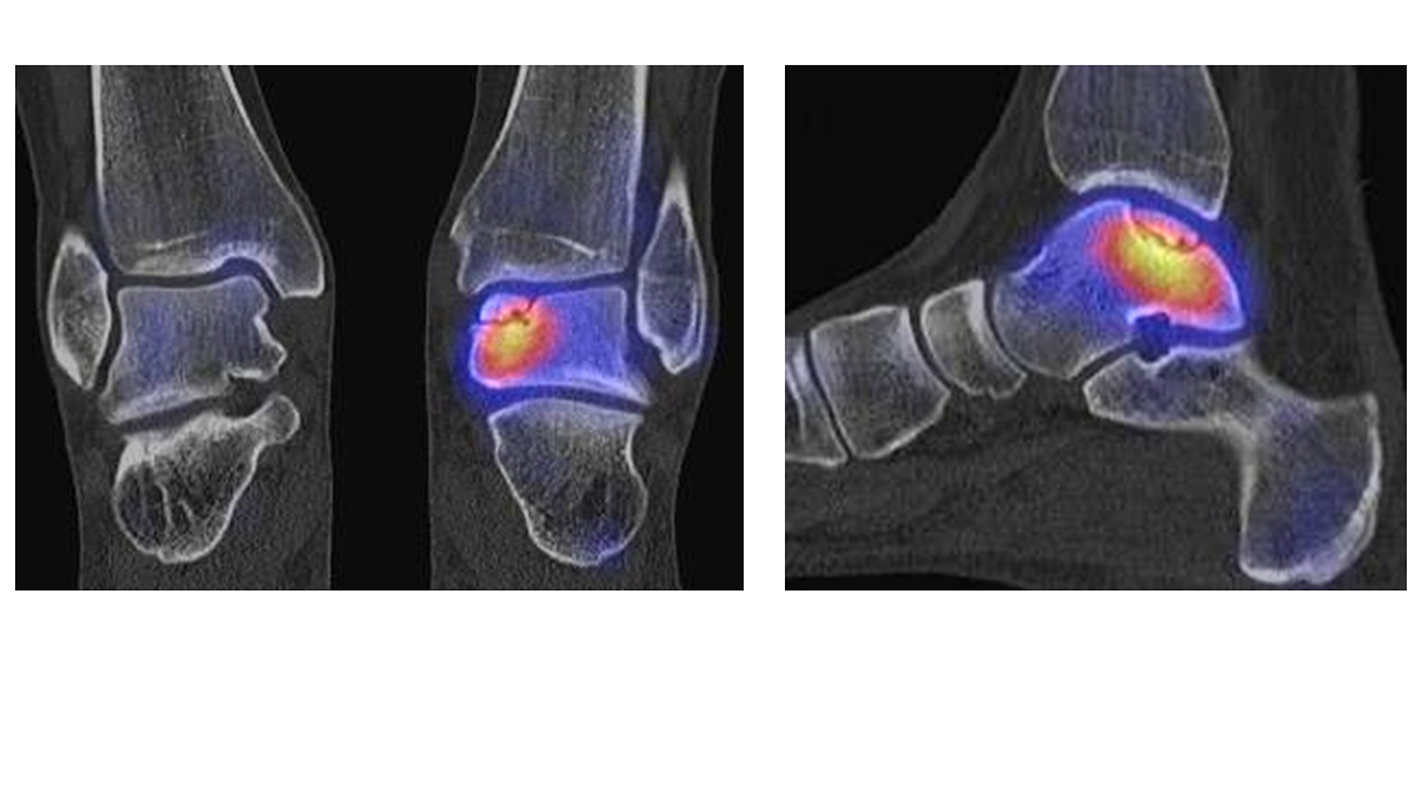

Abbildung 2.2.

Bilder eines Patienten mit Z. n. mehrfachen Sprunggelenksdistorsionen in der Vergangenheit, besonders heftige Distorsion des linken Sprunggelenkes 5 Wochen vor der Untersuchung. Die SPECT/CT zeigt eine instabile osteochondrale Läsion mit deutlicher Aktivierung.